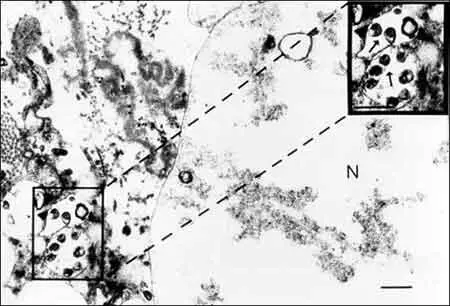

Атеросклероз — этиологическая роль в его развитии доказана для бактерии Chlamydia pneumoniae, хорошо известной как причина различных респираторных болезней. Сероэпидемиологические исследования показали ассоциацию антител к С. pneumoniae с атеросклерозом коронарных, сонных и церебральных артерий, а также инфарктом миокарда. С. pneumoniae была выделена из коронарных и каротидных атероматических бляшек (рис. 70).

Рис. 70. Ультраструктурные доказательства присутствия Chlamydia pneumoniae в коронарной атероме. Трансмиссионная электронная микрофотография демонстрирует присутствие в ткани коронарной атеромы эндосом, содержащих С. pneumoniae — тельца грушевидной формы [Lee Ann Campbell et al., 1998].

В опытах на животных показана роль этой бактерии в инициации и прогрессировании кардиоваскулярной патологии. Установление этиологического агента позволило изменить подходы к лечению атеросклероза и его осложнений. Например, показана терапевтическая эффективность антител к С. pneumoniae и антибиотика азитромицина при лечении больных с последствиями инфаркта миокарда [Lee Ann Campbell et al., 1998; Cassell G.H., 1998]